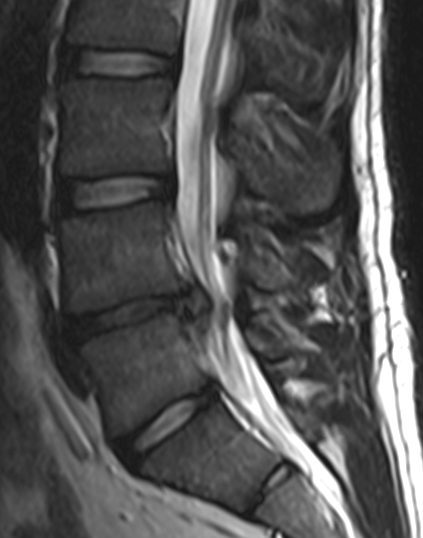

Hình ảnh đau vai gáy do thoát vị đĩa đệm cột sống cổ, đang khám tại phòng khám đông y Bảo Minh.

Chụp MRI là cách phát hiện thoát vị đĩa đệm cột sống chính xác nhất

Đau cột sống lưng, cột sống cổ, tê bì chân tay....coi chừng bạn bị thoát vị đĩa đệm cột sống. Cách phát hiện và chẩn đoán hiệu quả nhất căn bệnh thoát vị đĩa đệm chính là chụp MRI cột sống (chụp cộng hưởng từ).❮ đọc tiếp ❯ -